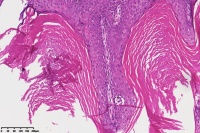

脂溢性角化症伴皮角?

女

年龄

49岁

手臂皮肤组织

图2

脂溢性角化病